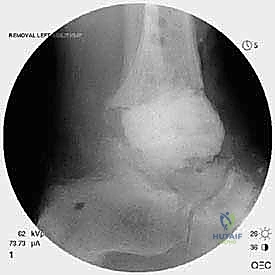

تُعد جراحة مراجعة مفصل الكاحل الصناعي (Revision Total Ankle Replacement) من الإجراءات الجراحية المتقدمة والبالغة الدقة في عالم جراحة العظام الحديثة. لا تقتصر هذه الجراحة على مجرد استبدال مفصل تالف بآخر جديد، بل هي عملية إنقاذ معقدة للغاية تهدف إلى معالجة المشاكل الميكانيكية والبيولوجية التي تنشأ بعد الجراحة الأولية. من أبرز هذه المشاكل: الفشل الميكانيكي للمفصل، تحلل العظام (Osteolysis)، أو حدوث كسور معقدة في الكعبين (Malleolar Fractures) المحيطة بالمفصل الصناعي. يتطلب هذا الإجراء تقييماً سريرياً وشعاعياً دقيقاً يشمل التصوير المقطعي ثلاثي الأبعاد والأشعة السينية، يليه تدخل جراحي دقيق لاستعادة التوازن الحيوي والميكانيكي للكاحل والحفاظ على الطرف من البتر أو الدمج.

- التخلخل العقيم (Aseptic Loosening): وهو السبب الأكثر شيوعاً. يحدث نتيجة تآكل البولي إيثيلين (البلاستيك الطبي) الموجود بين المكونات المعدنية، مما يولد جزيئات دقيقة تهاجمها خلايا الجسم المناعية، وتؤدي بالخطأ إلى تذويب العظم المحيط بالمفصل.

- هبوط المفصل (Subsidence): غوص المكون المعدني داخل عظمة الكاحل (Talus) أو عظمة الساق بسبب ضعف كثافة العظام.

- التصوير المقطعي المحوسب (CT Scan): وهو الأداة الذهبية لتقييم "المخزون العظمي" (Bone Stock). يوضح بدقة حجم الأكياس العظمية ومقدار العظم المفقود الذي سيحتاج لترقيع.

الخطوة الثالثة: إزالة المفصل القديم (Explant Removal)

يتم استخراج المكونات المعدنية والبلاستيكية لمفصل (Agility) القديم بحرص بالغ للحفاظ على ما تبقى من العظم السليم.